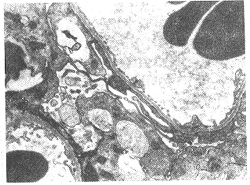

肾病综合征大鼠模型的建立及酶酚酸酯对其作用的实验研究

肾病综合征大鼠模型的建立及酶酚酸酯对其作用的实验研究中国免疫学杂志 2000年第12期第16卷 临床免疫学作者:毕黎琦 刘晓敏 何